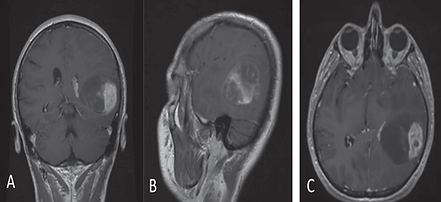

Çekilen beyin MR'ında (manyetik rezonans görüntüleme) sol temporal ve parietal bölgede, yani beynin şakak ve yan-arka kısmında, glial tümör morfolojisiyle uyumlu bir kitle saptandı. Kitle, hem kistik (sıvı dolu) hem de kanamalı bileşenler içeriyordu. Bu tür kanamalı pilositik astrositomlar (HPA), yetişkinlerde nadir görülen tümörlerdir.

Ameliyat öncesi kontrastlı T1 ağırlıklı MR görüntülerinde tümörün konumu ve boyutu Tümörün kanamalı ve kistik bileşenlerini gösteren ameliyat öncesi aksiyal MR görüntüleri.